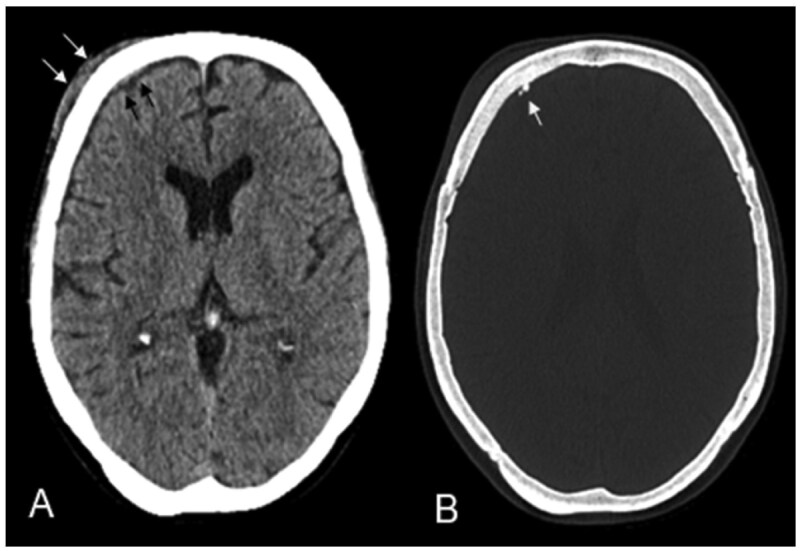

Primary central nervous system (CNS) mucosa-associated lymphoid tissue (MALT) lymphoma is a rare condition frequently mistaken for meningioma. Since these conditions require distinct treatment approaches, recognizing their imaging characteristics is essential for accurate clinical decision-making. A 69-year-old woman presented with headaches and forehead swelling, prompting MRI of the CNS. Suspecting an intracranial meningioma, the tumour board recommended surgical resection. However, histopathological analysis identified the lesion as a primary CNS MALT lymphoma. Follow-up revealed secondary cutaneous tumour infiltration, leading to a delay in adjuvant radiotherapy. Understanding the differential diagnoses of meningioma is critical for neuroradiologists and neurosurgeons to ensure appropriate treatment planning. This case highlights a misdiagnosis of meningioma that was ultimately identified as a primary CNS MALT lymphoma, emphasizing key imaging and clinical characteristics essential for distinguishing between the most important differential diagnoses of primary CNS MALT lymphoma.